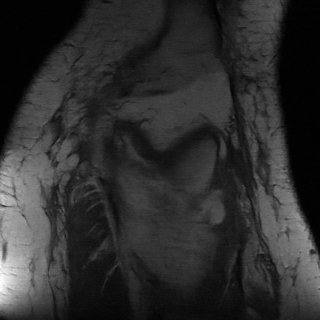

We compared all models on the validation and test set using the metrics suggested in Zbontar et al. [28]. A summary of this comparison can be found in table 2. Both i-RIM models consistently outperform the baselines. At the time of this writing, all three models sit on top of the challenge’s Single-Coil leaderboard.222http://fastmri.org/leaderboards, Team Name: NeurIPS_Anon; Model aliases: RIM - model_a, i-RIM 2D - model_b, i-RIM 3D - model_c. See Supplement for screenshot. The i-RIM 3D shows almost as good performance as it’s 2D counterpart and we believe that with more engineering and longer training it has the potential to outperform the 2D model. A qualitative assessment of reconstructions of a single slice can be found in figure 3. We chose this slice because it contains a lot of details which emphasize the differences across models.

Refer to caption

(a) Target Image

(b) U-Net 4x

(c) RIM 4x

(d) i-RIM 4x

(e) i-RIM 3D 4x

(f) Target Image

(g) U-Net 8x

(h) RIM 8x

(i) i-RIM 8x

(j) i-RIM 3D 8x

Figure 3: Reconstructions of a central slice in volume ’file1001458.h5’ from the validation set. Top: 4x acceleration. Bottom: 8x acceleration. Zoom in for better viewing experience.